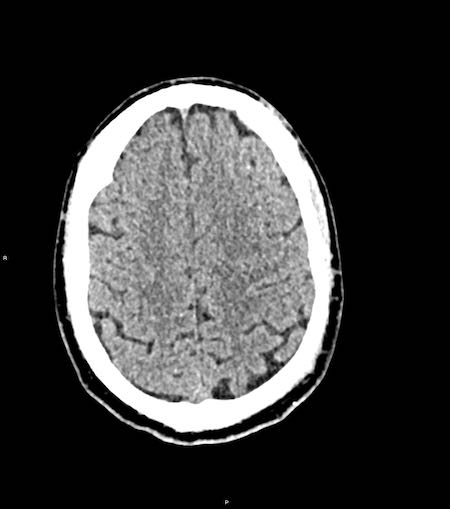

Tụ máu dưới màng cứng đồng tỷ trọng

Khi tụ máu dưới màng cứng tiến triển theo thời gian, tỷ trọng của khối tụ máu sẽ giảm dần và có thể tương đương với tỷ trọng của nhu mô não, khiến việc phát hiện tổn thương trở nên khó khăn.

Đây là trường hợp tụ máu dưới màng cứng đồng tỷ trọng rất khó phát hiện (các mũi tên).

Lưu ý rằng ở mức cắt cao hơn có tụ máu dưới màng cứng hai bên.